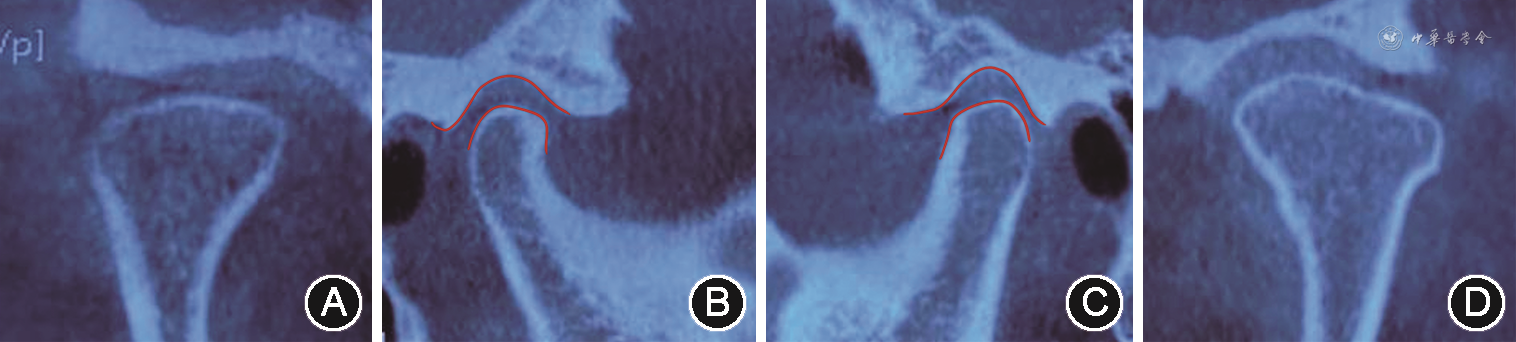

垫后关节CT A:右侧髁突冠状位;B:右侧髁突矢状位,红色线条间空隙示右侧颞下颌关节前间隙较治疗前缩小;C:左侧髁突矢状位,红色线条间空隙示左侧颞下颌关节前间隙较治疗前增大;D:左侧髁突冠状位

垫后关节CT A:右侧髁突冠状位;B:右侧髁突矢状位,红色线条间空隙示右侧颞下颌关节前间隙较治疗前缩小;C:左侧髁突矢状位,红色线条间空隙示左侧颞下颌关节前间隙较治疗前增大;D:左侧髁突冠状位(4)诊断性临时修复:借助电子面弓记录患者关节及下颌运动轨迹,获取个性化动态数据(左侧方8.1 mm,右侧方9.9 mm;前伸4.6 mm;侧方髁道右侧14.1 mm,左侧14.2 mm;侧方髁道斜度右侧44°,左侧29°),通过多次开闭口运动,寻找患者的正中关系并记录颌位关系。最后根据这些参数调整虚拟